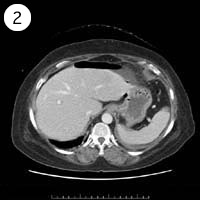

57歳 女性

単純CT

造影CT